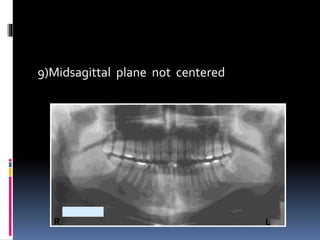

9)Midsagittal plane not centered

R L